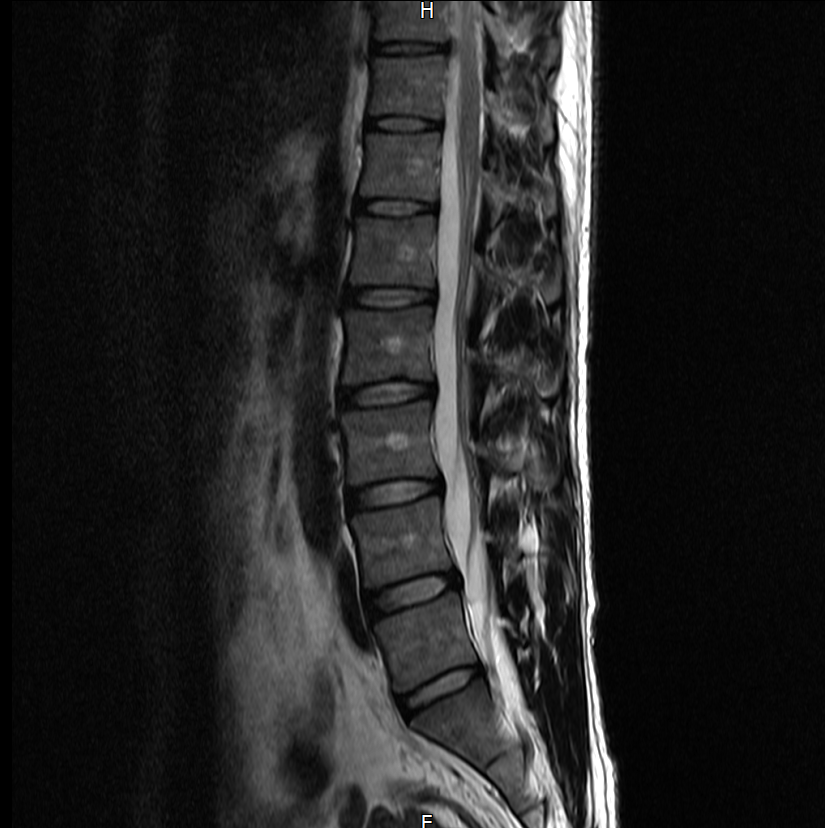

아래는 저의 경추과 요추 MRI 사진 첨부합니다.

※우리들병원 (신경외과 대표원장) : 경추,요추 MRI 촬영했고 요추는 매우 건강하고 경추에는 일자목에 퇴행성 디스크가 보이지만 한쪽팔에 저림이나 힘빠짐을 유발할 정도는 절대아니고, 다른 원인을 찾아야한다고 했습니다.

※분당서울대병원 재활의학과 : 근전도검사 이상없음, 경추 요추 MRI를 봐도 근골격계 문제로 보기 어렵다. 신경계 문제도 아니다.

3명이 디스크가 아니라고 하는데 1명이 디스크일수 있다고 하니까 조금 어렵습니다. 경추디스크가 약간은 있으니 팔저림은 설명할수 있다해도 다리저림은 설명이 안됩니다.. MRI 결과상 요추는 매우 건강하다고 하셨거든요.